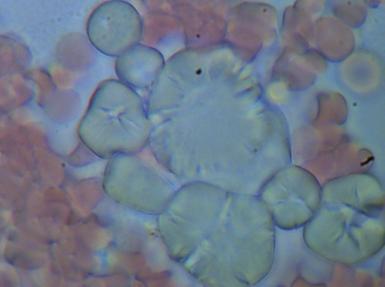

1.CHOLESTEROL

Podczas badania często stwierdzana jest obecność kryształków cholesterolu. W zależności od ich wielkości możemy określić zagrożenie rozwoju miażdżycy, wystąpienia zawału czy zakrzepu. Nawet jeżeli wartości biochemiczne mieszczą się w normie to przede wszystkim wielkość a w mniejszym stopniu ilość blach cholesterolowych zwiększa ryzyko wystąpienia choroby.

Powiększenie 1600x - aby wykonać zdjęcie całej blachy trzeba było wykonać cztery zdjęcia.